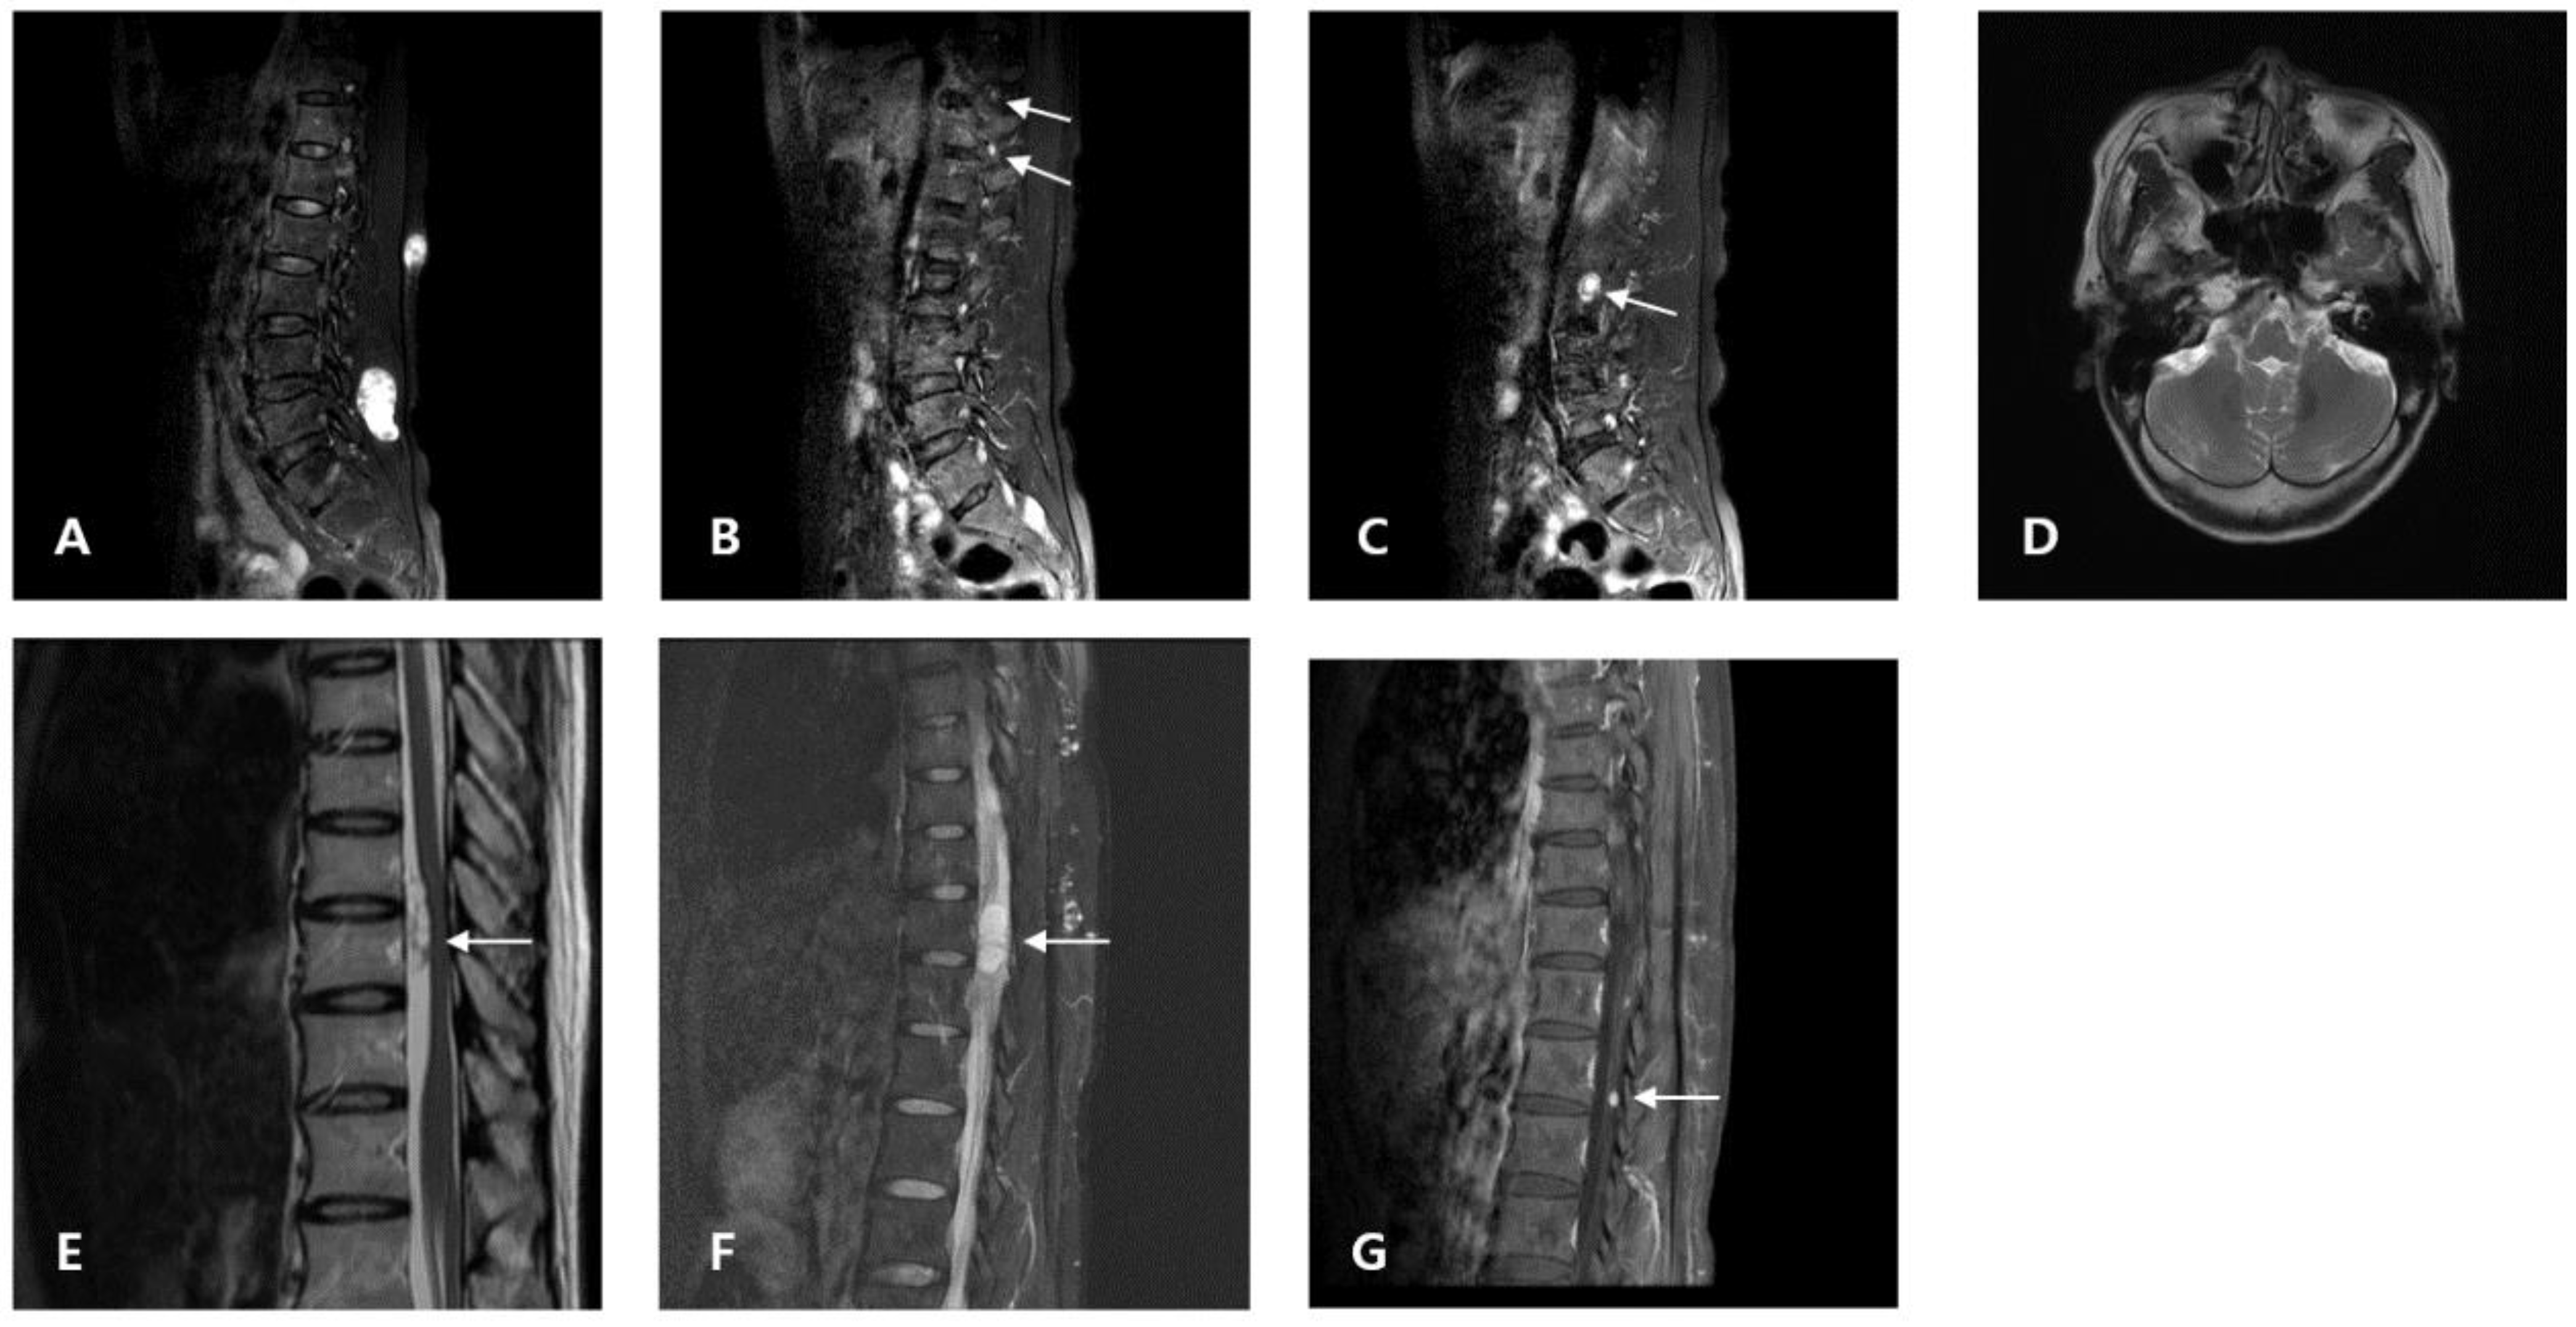

Figure 1.

Proband (A–D): (A) T2-weighted sagittal MRI from 2021 showing a tumor (41.82 mm) with cystic degeneration in the lumbar level. Excisional operation was performed. (B,C) T2-weighted sagittal MRI from 2021 showing enhanced dots in the paraspinal connective tissue at the lumbar level (arrow). (D) Brain MRI showed no evidence of vestibular schwannomas. Daughter (E–G): (E) T2-weighted MRI from 2008 showing an intradural extramedullary tumor (T10–T11). (F) T2-weighted MRI from 2015 showing an intradural extramedullary tumor (T11–T12). (G) T2-weighted MRI from 2021 revealing an enhanced dot in the cauda equina (L1).

The patient (proband)’s daughter, a 45-year-old woman, came to seek medical attention because of her family history. She had received treatment from other hospitals prior to the visit. After a review of accessible medical records, we found that the patient had an operational history of spinal intradural extramedullary schwannoma on the thoracic spine (T10–T11). She had severe preoperative left flank pain. In 2015, she was re-admitted to the hospital because of severe left flank pain. Spinal MRI revealed a neurogenic tumor at the T11–T12 level. Other imaging modalities did not reveal any extraspinal schwannomas. Excisional removal of the spinal tumor was performed. Intradural extramedullary schwannoma with calcification was pathologically confirmed. In 2021, spinal MRI revealed an enhanced dot in the cauda equina (L1), suggestive of a migratory process (Figure 2). The patient did not report any pain. Physical examination revealed no hearing deficits. The daughter was clinically diagnosed with schwannomatosis. Phenotypic differences between the proband and the daughter are stated in Table 1.